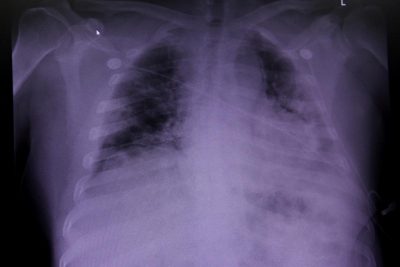

- Раніше пульмонолог та хірург органів грудної клітини Євген Симонець говорив, що при запаленні легень, спровокованому коронавірусом COVID-19, є важлива особливість – не чути хрипи.

- Медик додав, що для діагностики коронавірусної пневмонії потрібно робити комп'ютерну томографію.